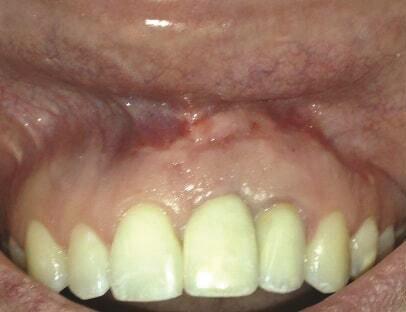

Пациент 1: Пациентка 30 лет с неосложненным медицинским анамнезом обратилась с имплантатом № 2.1, у которого диагностирован ретроградный периимплантит. Зуб № 2.1 был заменен имплантатом 8 лет назад из-за травмы в анамнезе и неудачного лечения корневых каналов. Имплантат демонстрировал периапикальную рентгенопрозрачность со свищевым ходом, ведущим к верхушке имплантата № 2.1 (Фото 1 и Фото 2). У пациентки была высокая линия улыбки с более длинными клиническими коронками зубов №№ 2.1 и 2.2 по сравнению с №№ 1.2 и 1.1 (Фото 1 и Фото 2).

Фото 1 и Фото 2. Случай 1: Первоначальная клиническая картина с гуттаперчевым штифтом, установленным в апикальный свищ зуба № 2.1 (Фото. 1); рентгеновский снимок, показывающий гуттаперчевый штифт, ведущий к периапикальному поражению (Фото. 2).